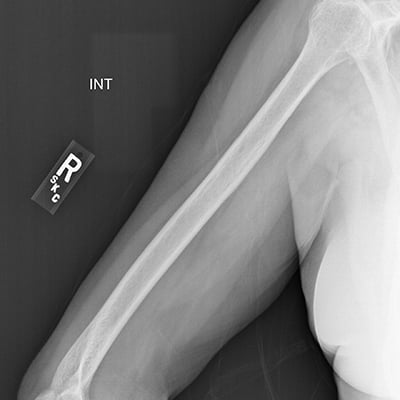

This module will help you achieve optimal images when performing elbow, humerus, shoulder, and scapula examinations. Patient preparation and positioning are discussed, as well as technical settings and patient instructions. Descriptions and images of the expected anatomical structures are included, as well as image evaluation criteria.